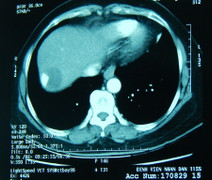

Các bác sĩ Khoa Ngoại Gan Mật Tụy, Bệnh viện K Trung ương cơ sở Tân Triều vừa phẫu thuật cứu sống một bệnh nhân có khối u gan với đường kính gần 30 x 20cm.